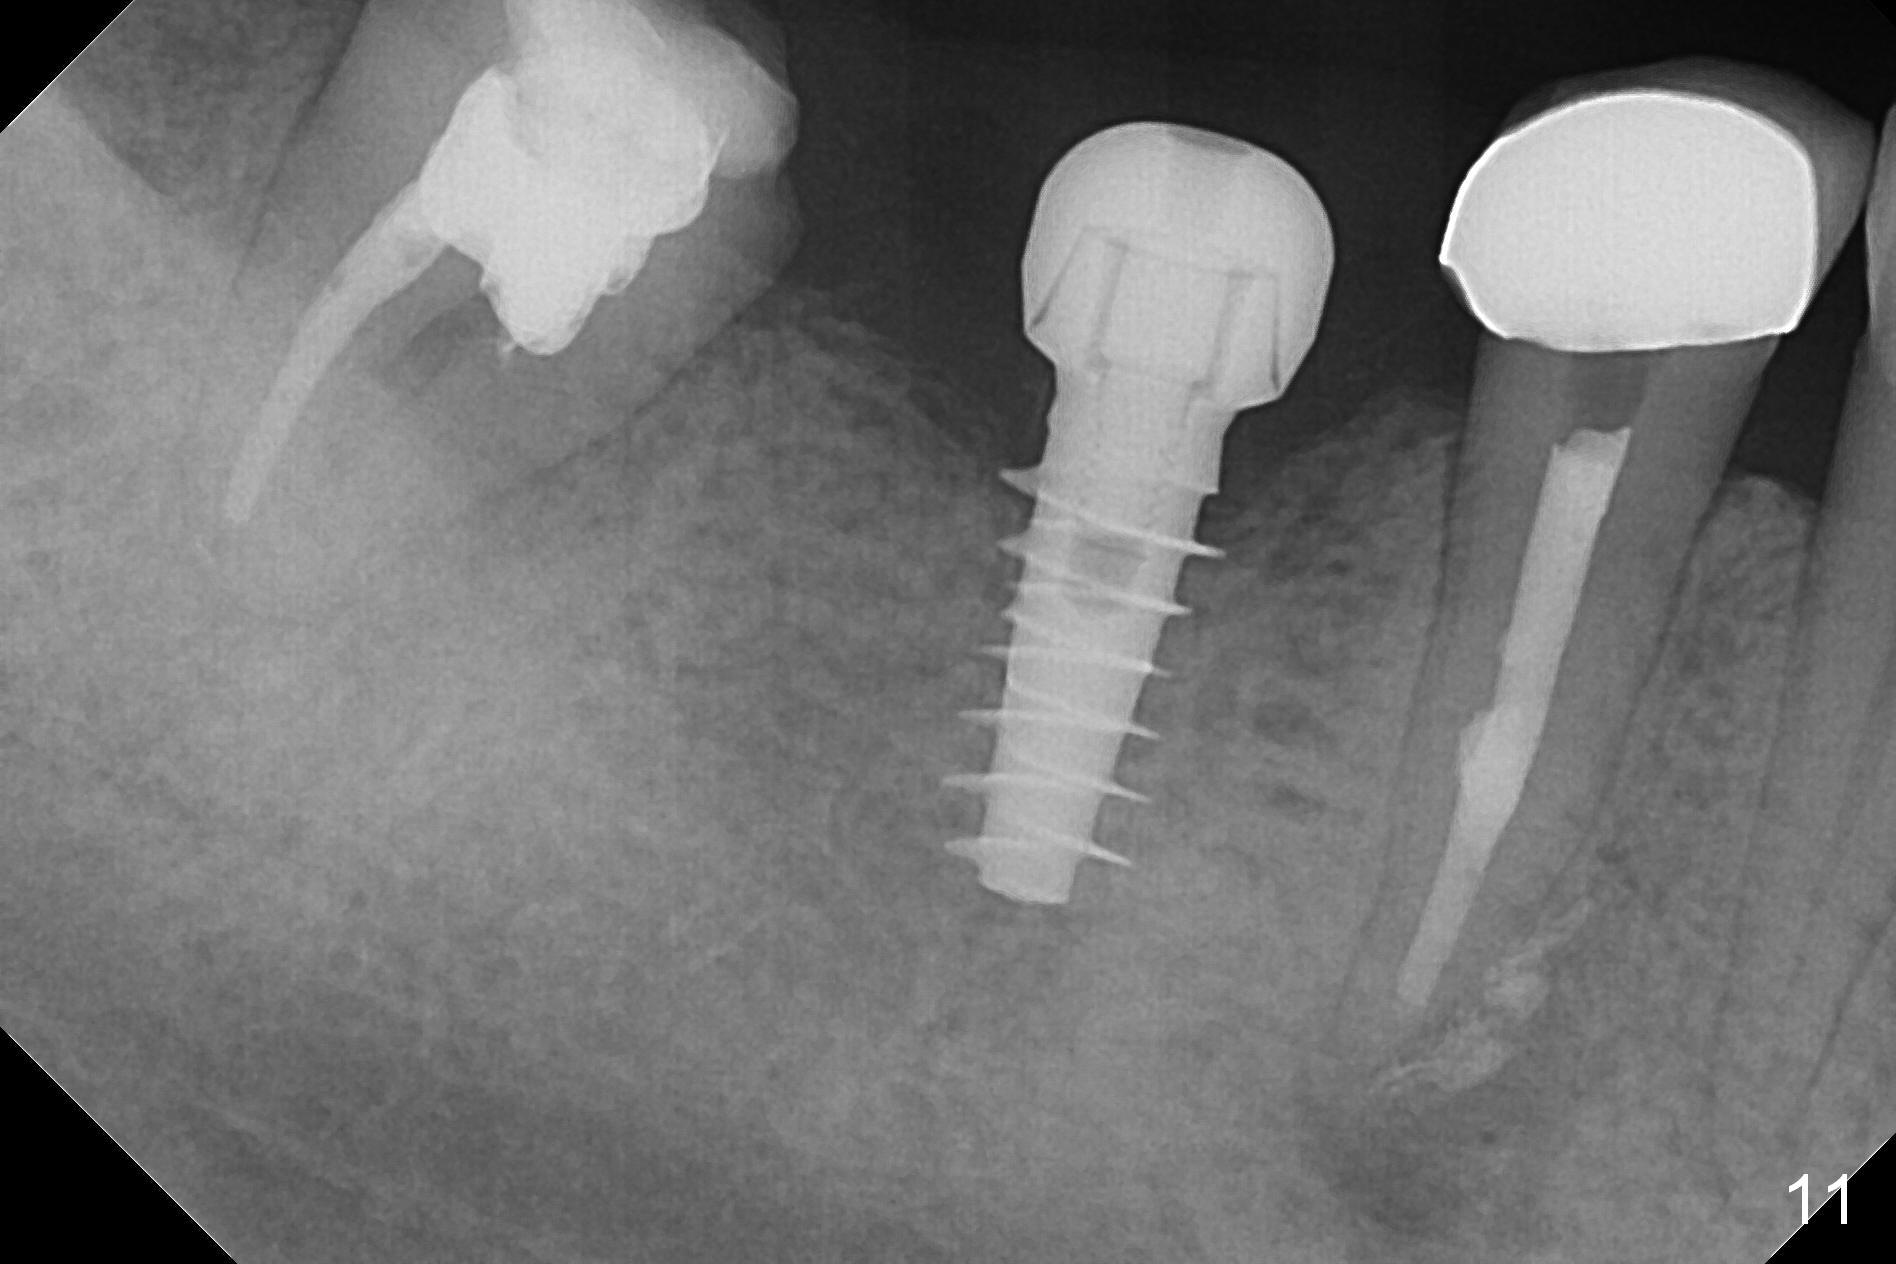

Splinted provisional is fabricated #30 and 31 one month postop. The patient returns for final restoration (single units) nearly 4 months postop (Fig.11). Since the margin is subgingival, a screw type crown is fabricated for #30 (Fig.12). The buccal gingiva looks convex after healing cap removal (Fig.13, as compared to Fig.4 (concave)). PA is taken immediately post tightening and cementation (Fig.14, 5 months postop). It appears that new bone has grown between the most coronal threads (arrows). The bone density immediately around the implant appears to increase 1.5 years post cementation (Fig.15,16). She returns because of failure of 18-20 bridge (implants will be placed at 18/19). The implant at #30 is in fact not placed deep enough; the coronal threads seem to be exposed, although there is no periimplantitis (Fig.17 CT). The tooth #31 is symptomatic; the mesial canal is missing (Fig.18 M, <). The gingiva around the crowns at #30 and 31 remains healthy 2 years 4 months post cementation (Fig.19). Metal exposure of the crown at #31 is intentional. Occlusal reduction is done to alleviate periapical re-infection (Fig.18).